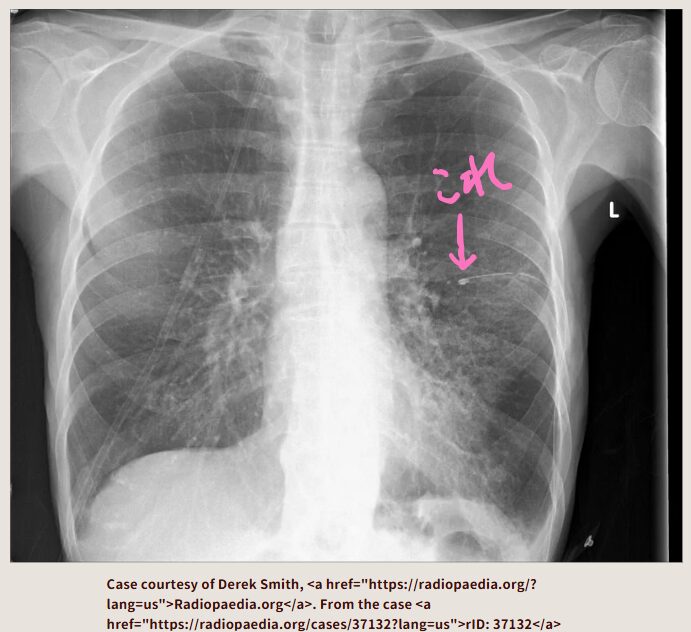

この胸部レントゲンはどうでしょうか? 左の肺の外側が黒っぽいですよね。

左の気胸になっています。

アスピレーションチューブを左胸腔に留置して、脱気しています。それで左肺が膨らんでいます。